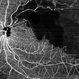

- CNP areas, takayasu arteritis

- A case of 16 year-old female with combined RD in RE. Fundus examination & FFA revealed 360 degrees non-perfusion in periphery in non-symptomatic eye.